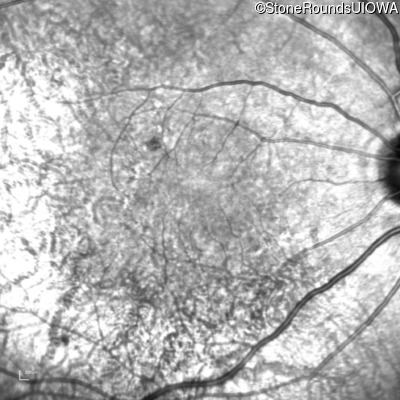

Age at visit: 58 years

OD OS

This 58 year old completely asymptomatic man had pigmentary changes on his last retinal exam.